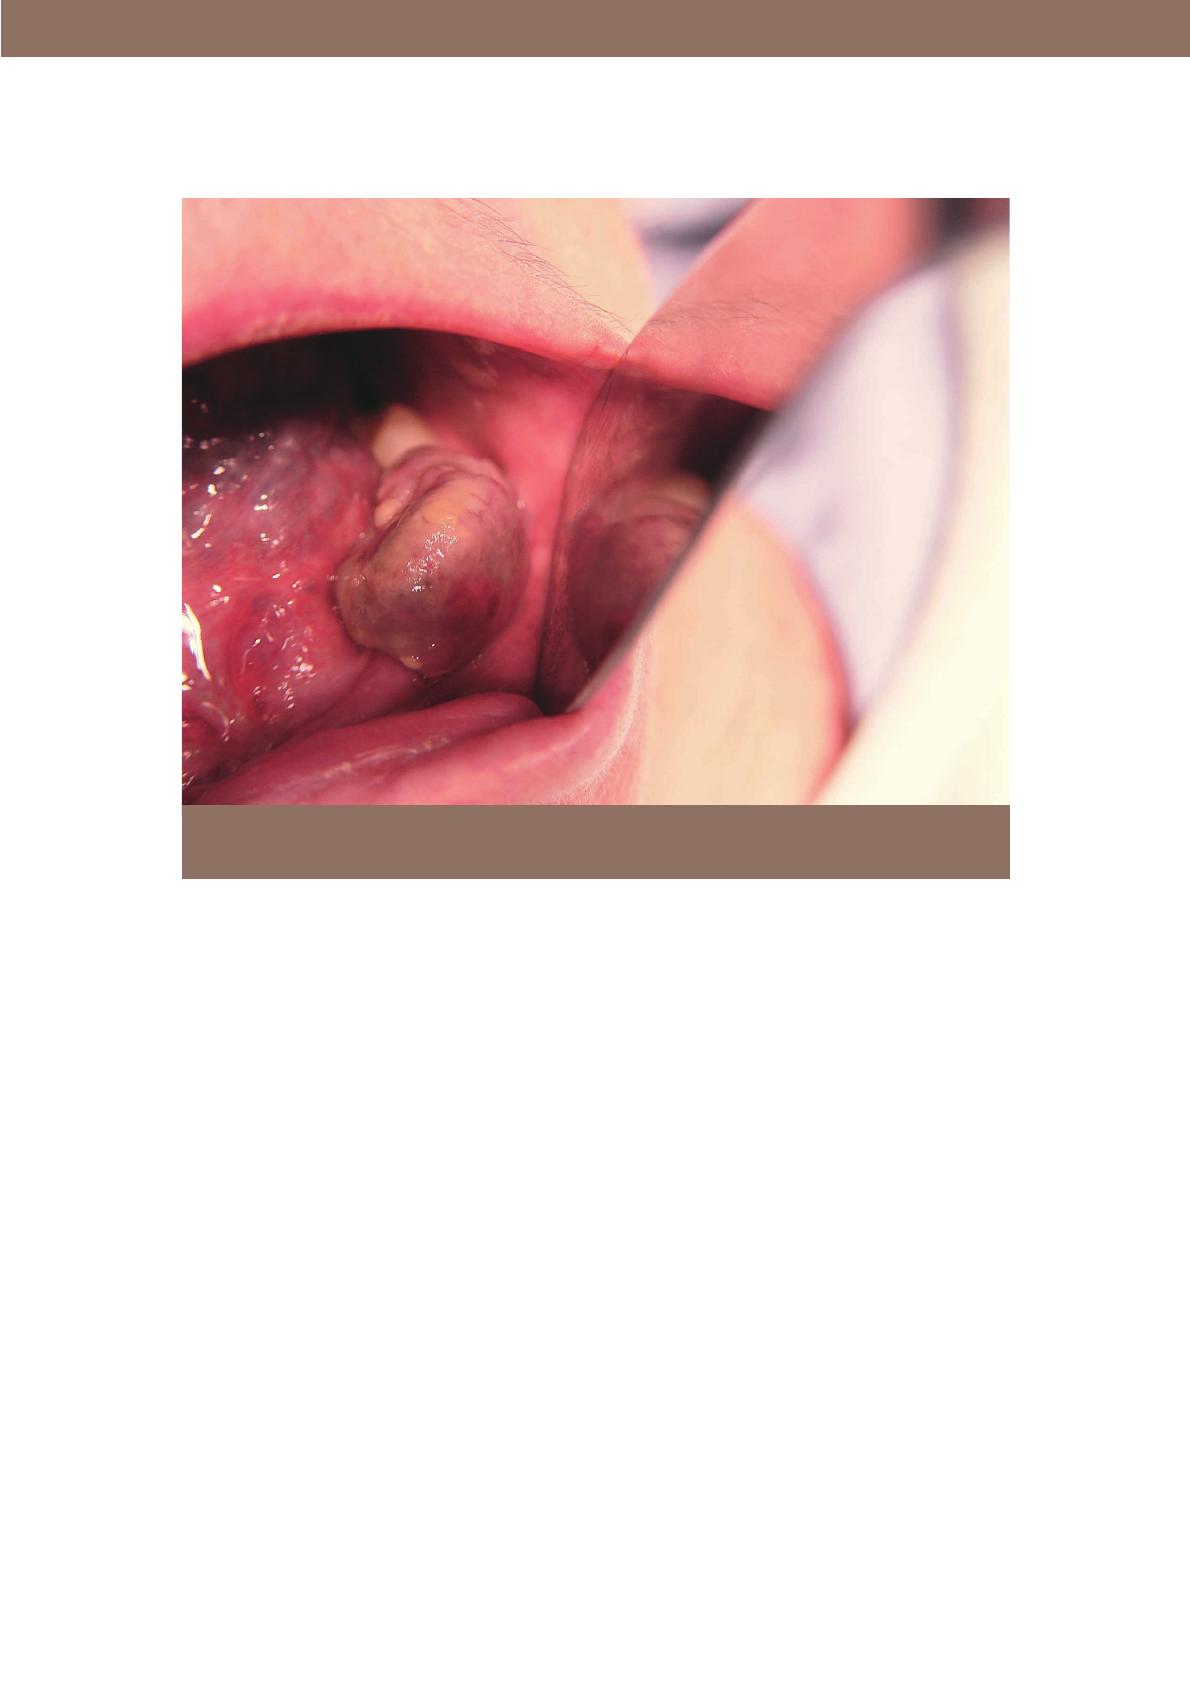

masse d’allure hyperplasique : de couleur

rouge-rose à pourpre, très souvent sessile,

ferme et élastique, souvent indolore sponta-

nément, parfois très vascularisée avec pré-

sence de télangiectasies [39-48]. Elle est ulcé-

rée dans 10 % des cas [38]. Sa croissance est

continue, si bien qu’elle interfère rapide-

ment avec les fonctions manducatrices. Dans

ce cas, les traumatismes répétés provoquent

des douleurs et des saignements (fig. 1).

Fig. 1 Métastase gingivale d’un sarcome à cellules fusiformes des parties molles du coude.

Iconographie : Dr Cédric Desandes, Centre Georges-François Leclerc, Dijon.